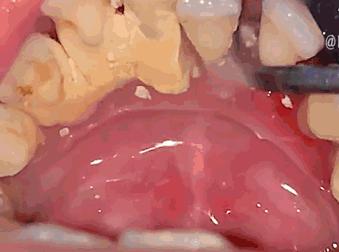

牙结石从软垢,逐渐钙化变硬附着在牙齿表面,成分有磷酸钙、水、碳酸钙等等。通常存在于唾液腺开口处的牙齿表面。如下颚前牙的舌侧表面,上排后牙的表面和牙齿颈部等等。

随着时间的推移越积越多、越积越厚,并逐渐向牙颈部位发展,形成更为隐形也更为可怕的“龈下结石”。

牙结石从牙冠逐渐向下蔓延,牙结石每进步一些,牙槽骨就萎缩一些,久而久之,牙齿就逐渐松动,牙结石便见缝插针,逐渐蔓延到牙根部位。

对口腔而言,结石是一种异物,它的存在本身就会不断刺激牙周组织并压迫牙龈,影响口腔局部血液循环,造成牙周组织病菌感染,引起牙龈发炎萎缩,形成牙周袋。